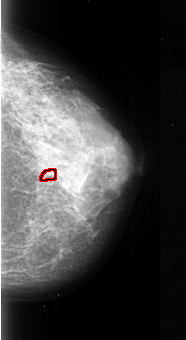

A_1037_1.LEFT_MLO

LEFT_MLO LINES 5491 PIXELS_PER_LINE 2551 BITS_PER_PIXEL 16 RESOLUTION 42 NON_OVERLAY

FILE: A_1037_1.RIGHT_MLO.OVERLAY

TOTAL_ABNORMALITIES 1

ABNORMALITY 1

LESION_TYPE CALCIFICATION TYPE PLEOMORPHIC DISTRIBUTION CLUSTERED

ASSESSMENT 4

SUBTLETY 1

PATHOLOGY MALIGNANT

TOTAL_OUTLINES 1

BOUNDARY